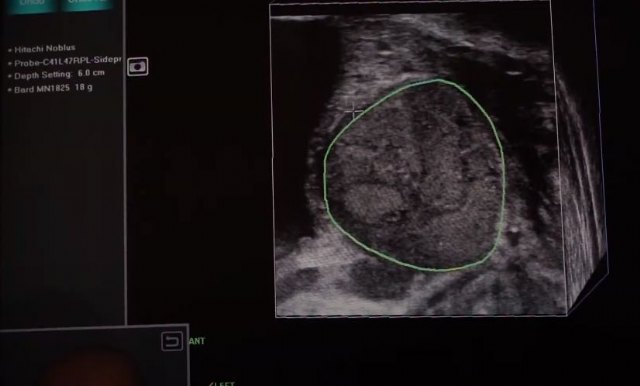

Antes de la utilización de la innovadora técnica láser, el paciente debe someterse a una biopsia prostática robotizada por fusión para detectar con precisión el tumor.

El doctor Jorge Rioja, urólogo de Policlínica Sagasta y experto en el tratamiento del cáncer de próstata, apunta que “la biopsia prostática por fusión mediante el Robot Artemis es un elemento diagnóstico esencial para localizar el tumor de forma precisa”.

Cruz Blanca es el primer y único grupo médico en utiliza el Robot Artemis, un equipo robotizado de última generación que permite puncionar en una sola intervención las lesiones de próstata. Este robot fusiona imágenes de ecografía y resonancia magnética (RM) que permiten detectar y delimitar con precisión los nódulos sospechosos.

En el caso que el diagnóstico de estos nódulos fuera positivo, se procedería a su eliminación. Esto se consigue utilizando ambas técnicas a la vez, así el robot guía al láser hasta el foco de la lesión para realizar una terapia lo más focal posible y con menores efectos secundarios.